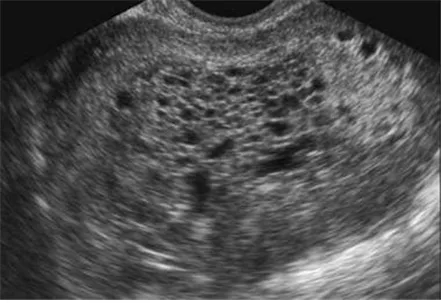

US: snowstorm pattern

Imp: 포상기태(hydatidiform mole)

초음파 상 snowstorm pattern이 관찰되어 포상기태 의심 하 진단 및 조직학적 감별을 위하여 자궁내막소파술을 시행한다.

• 질출혈로 내원한 여성의 초음파 상 snowstorm pattern이 관찰된다.

• Urine hCG (+)이면 포상기태로 진단 가능하다.

• 가임기 여성이므로 흡입긁어냄술을 통해 조직학적 진단과 치료를 동시에 진행한다.